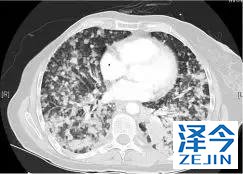

一位77岁的女性患有EPS15-NTRK1 IV期非小细胞肺癌,我们可以看到她的双肺满是病灶,并且出现了肝脏和脑转移,可以说是非常非常晚期了,

既往有乳腺癌史;

既往症状有厌食,乏力,咳嗽,高脂血症;

ECOG 1;

没有接受手术,放疗或化疗。

开始使用larotrectinib 100 mg BID并持续治疗,

第3周期开始:

肺靶病变达到缓解,我们可以明显的看到前后的图像,病灶明显缩小了,

脑转移病变显示缩小了95%!

初始, 2018年6月 3周期 2018年8月